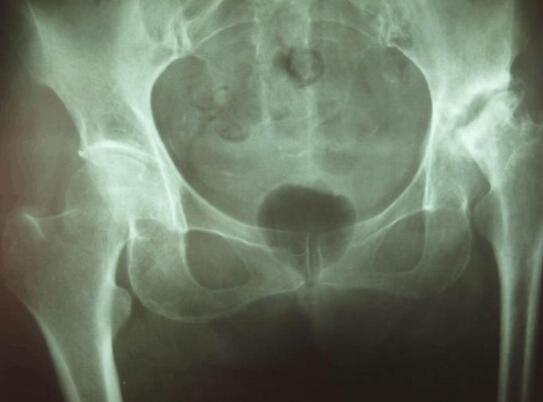

股骨头坏死属于日常生活中非常常见的一种疾病。多是由于股骨的颈骨折、髋关节的错位、长期的激素使用、或者是长期的喝酒等一系列的原因,引起了股骨头坏死的情况发生。出现股骨头坏死的疾病, 是比较艰难的,会导致髋关节出现疼痛、功能障碍、跛行等症状的发生。郑州痛风风湿病骨科医院好不好,河南专业治疗股骨头坏死

出现股骨头坏死的情况,一般是不影响到生孩子的,但是如果正处于股骨头坏死治疗的阶段,正处于吃药,建议先暂时性的不要怀孕,因为怀孕以后会加重髋关节的股骨头的负担,从而加重病情。出现股骨头坏死的情况,建议去正规医院的妇科或者是骨科进行相关的检查,根据检查结果,采取一定的治疗措施,缓解了病情或者是 了以后再考虑要孩子。